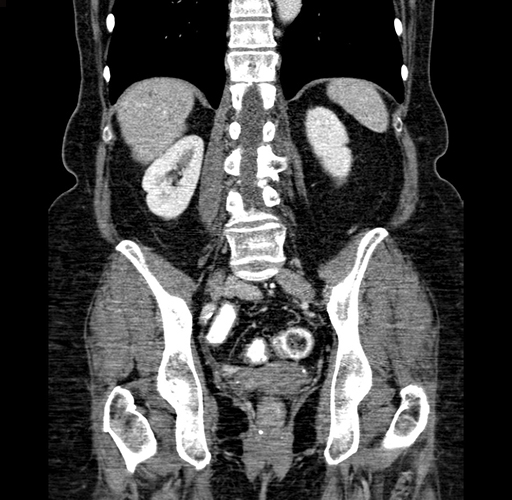

Pre-Chemo: Coronal Venous

Coronal Venous